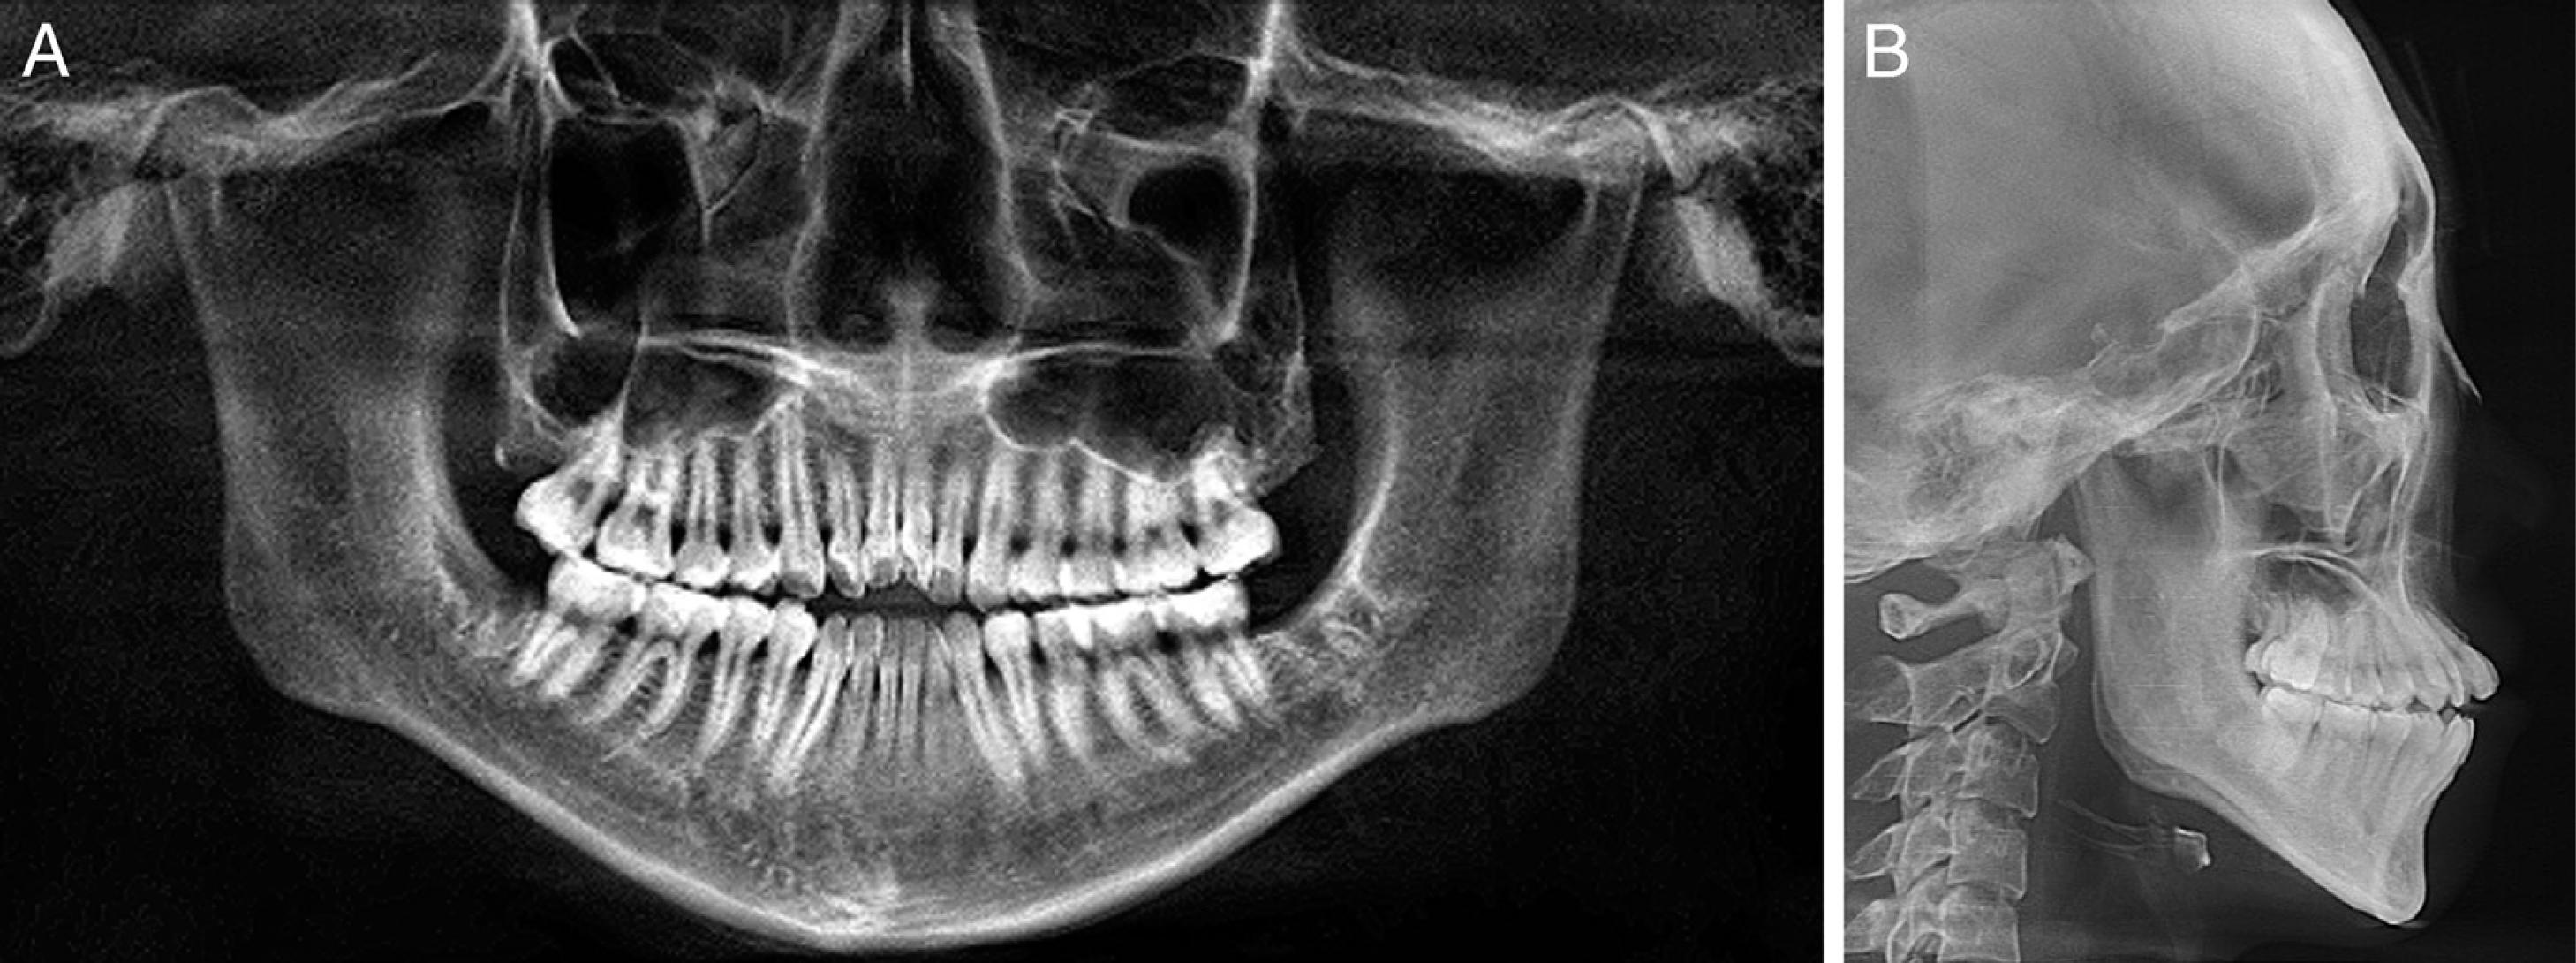

Figure 3.